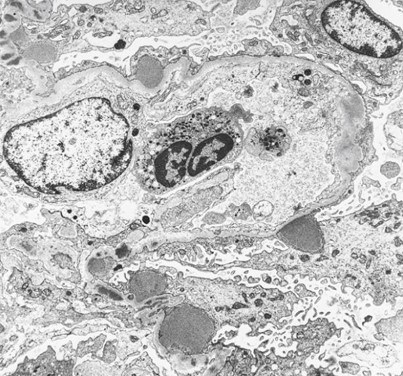

What is this and why?

Minimal Change Disease - podocyte foot process effacement